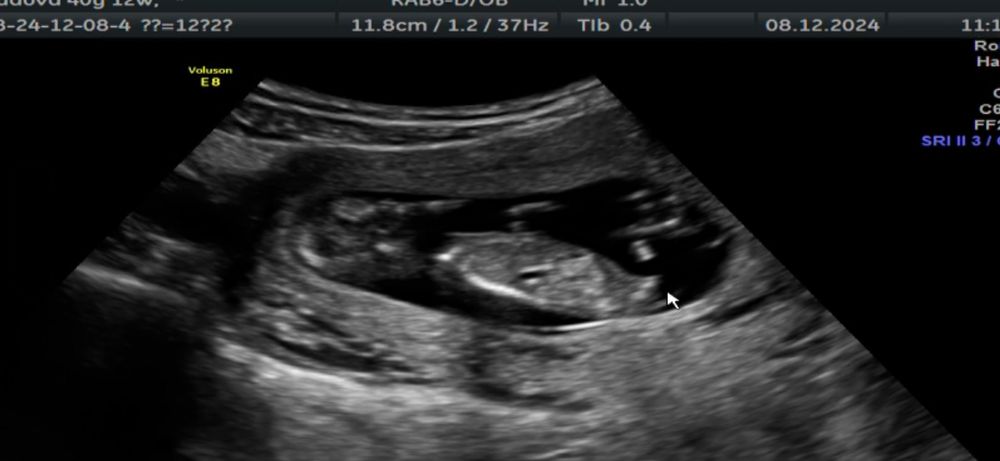

Узи 12 недель ❤️ Погадаем кто?

40 минут общения с нашей крошкой были наполнены смехом и улыбками. Спасибо вселенной за эти бесценные моменты.

У нас все хорошо, вопросов нет.

Врач сказал что может предположить пол лишь на 60%… Но так же интересно погадать 😅

Мне по половому бугорку видится девчуля… а вам?))